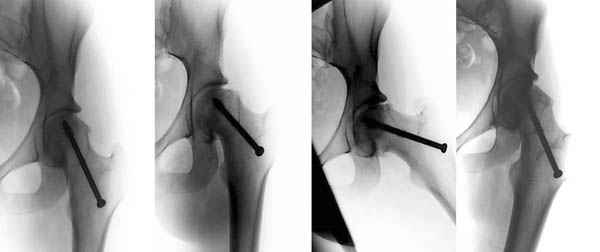

Ребёнок 14 лет. Весом под центнер. Имеющаяся рентгенологическая деформация деформация - на момент поступления. Госпитализирован ребёнок 14 лет. Мальчик, мягко говоря, крупный, гиперстенического типа сложения, ближе к десантнику. Весит 95 кг. Ожирение 2-й степени. Со слов больного - испытывает дискомфорт в области тазобедренного сустава в течение 3-х месяцев. На рентгенограммах - положение дел на момент поступления - конец мая. Укорочение конечности на 1,5 см. Ограничение внутренней ротации. Ходит, едва заметно прихрамывая на больную ногу. Эндокринологический статус находится в стадии обследования. Выполнена рентгенография в стандартных укладках, спиральная КТГ.Ясное дело, головка бедра <ушла> вниз и кзади. Пытающаяся <поймать> её шейка варизировалась и исполнила ретроверсию, создав изгиб во фронтальной плоскости. На рентгеноскопии - подвижность головки не определяется. Мальчик имеет далеко идущие планы на обустройство собственной жизни и образование. Крайне негативно относится к длительной иммобилизации и консервативному лечению. Загодя не согласен со снижением качества жизни в процессе лечения. Мнения коллег относительно дальнейшего лечения разделились. Успешность репозиции головки под наркозом - сомнительная в связи с имеющейся деформацией шейки бедра. Одни склоняются к тактике невмешательства - разгрузка больной конечности, ФЗТ , массаж, и т.д. Предлагают ждать завершения процесса <сползания> головки в условиях полной разгрузки, <тянуть> сустав до эндопротезирования как можно дольше. Другая группа коллег предлагает немедленную стабилизацию головки, что, кажется, правильно. Принимая во внимание анатомическое соотношение головки и шейки бедра, способ остеосинтеза так же вызвал массу споров, не приведших к единому и окончательному мнению. Пока дискуссия остановилась на стабилизации спицами Бека под контролем ЭОП, возможно с применением электродов для проведения электростимуляции слабыми импульсными токами. Техника проведения спиц, однозначно, будет сопряжена с техническими трудностями, обусловленными имеющейся деформацией шейки. Как бы Вы поступили, коллеги, в данной ситуации?Заранее спасибо. И прошу прощения за качество спимков. Буду отправлять их по очереди.

Здравствуйте Данил. По представленным рентгенограммамам и кт срезам Вы имеете дело хронической, стабильной формой ЮЭГБК. Шеечно- эпифизарная деформация выраженная, эпифиз отклонён кзади более чем на 70 градусов, практически до упора в межвертельную ямку, что характеризует её как тяжёлую степень. В выборе метода лечения мы придерживаемся следующей схемы: